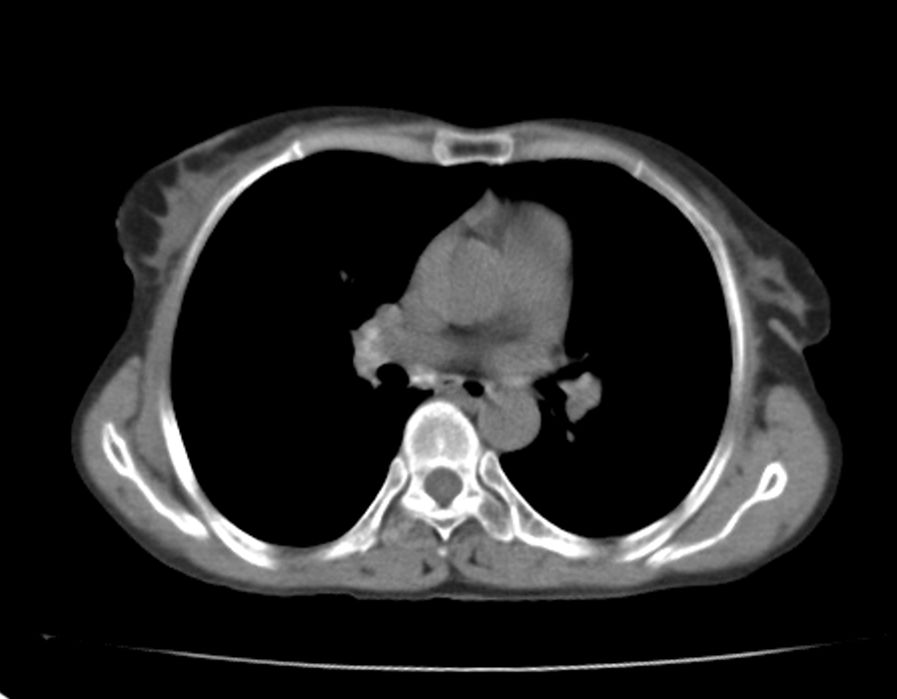

标题: CT21609:右乳包块1年,请各位讨论分析一下,乳腺CA, [打印本页]

标题: CT21609:右乳包块1年,请各位讨论分析一下,乳腺CA,

考虑---右乳癌并胸壁、肋骨、双肺转移。

考虑乳腺癌侵犯肋骨、胸壁及两肺转移可能性大。

右乳癌并胸壁、肋骨、双肺转移。

考虑右侧乳腺癌侵犯肋骨、胸壁及两肺转移。

支持考虑---右乳癌并胸壁、肋骨、双肺转移。

考虑右侧乳腺癌侵犯肋骨、胸壁及两肺转移可能。

考虑右侧乳癌并胸壁、肋骨及双肺多发性转移。